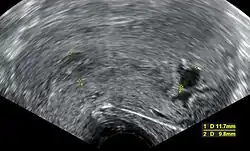

Ultrasound criteria

A review article in The New England Journal of Medicine based on a consensus meeting of the Society of Radiologists in Ultrasound in America (SRU) has suggested that miscarriage should be diagnosed only if any of the following criteria are met upon ultrasonography visualisation:[110]

| Miscarriage diagnosed | Miscarriage suspected | References |

|---|---|---|

| Crown-rump length of at least 7 mm and no heartbeat. | Crown–rump length of less than 7 mm and no heartbeat. | [110][111] |

| Mean gestational sac diameter of at least 25 mm and no embryo. | Mean gestational sac diameter of 16–24 mm and no embryo. | [110][111] |

| Absence of embryo with heartbeat at least 2 weeks after an ultrasound scan that showed a gestational sac without a yolk sac. | Absence of embryo with heartbeat 7–13 days after an ultrasound scan that showed a gestational sac without a yolk sac. | [110][111] |

| Absence of embryo with heartbeat at least 11 days after an ultrasound scan that showed a gestational sac with a yolk sac. | Absence of embryo with heartbeat 7–10 days after a scan that showed a gestational sac with a yolk sac. | [110][111] |

| Absence of embryo at least 6 weeks after last menstrual period. | [110][111] | |

| Amniotic sac seen adjacent to yolk sac, and with no visible embryo. | [110][111] | |

| Yolk sac of more than 7 mm. | [110][111] | |

| Small gestational sac compared to embryo size (less than 5 mm difference between mean sac diameter and crown-rump length). | [110][111] |